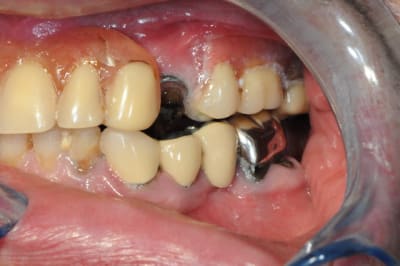

bien sure il faut tout revoir, l'occlusion, la DV, la courbe occlusale, la ligne du sourire...

extraction: 14-15-23-44 et 36 (ou amputation, mais à quoi bon ?)

reprendre la courbe occlusal avec des céram sur 43-46-33-34

bridge sur implant sur 44 -46 et 35-36 (ou 35-37?)

je ne vois pas ce qui vous choc en bas sinon qu'il faut peut être remplace

r aussi la 37 ?